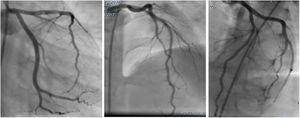

An emergency coronary angiography (CAG) was performed at admission, eight hours after chest pain onset and showed a massive thrombosis of the left anterior descending artery (LAD) with thrombolysis in myocardial infarction II flow (Figure 2). Tirofiban was injected into the LAD for thrombolysis during the CAG procedure.

The final diagnosis was STEMI with thromboembolism in the LAD. The patient continued to receive antithrombotic medication (aspirin, clopidogrel, tirofiban and heparin), nitrates, statins, diuretics, beta blockers, and a high dose of prednisolone to treat his decompensated NS. A CAG, performed after 7 days, revealed normal coronary artery flow and no more thrombosis (Figure 3). The patient was discharged after eight days in a stable hemodynamic condition. He was followed up by the pediatrician for immunosuppressive therapy. He continued to be stable and asymptomatic at 12-month follow-up. Echocardiogram revealed LVEF was 53%, which was better than before.